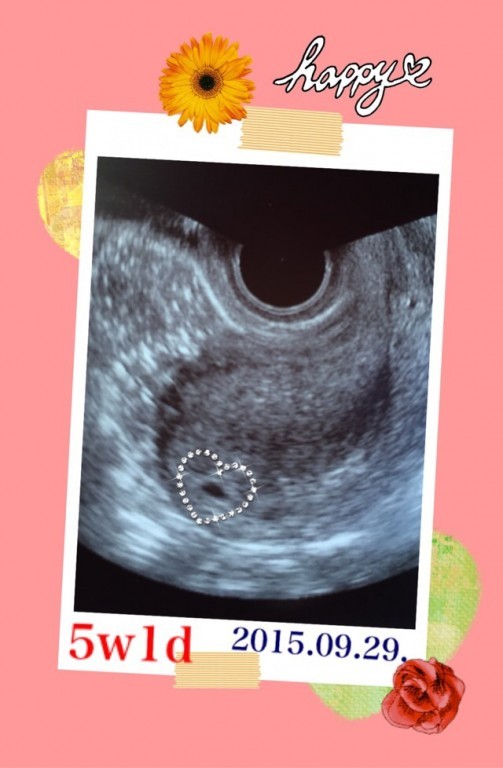

Web本日病院受診をし、胎嚢確認はできましたが小さいと言われました。 推定5週4日で69mmでした。 小さいから流産の可能性もある、 このまま成長してくれれば心配はなくなる また2週間後に来てくださいとのことでした。 今日妊娠発覚後初めての診察でした。 最終月経日から数えると5週3日目です。 胎嚢確認はできたのですが、47mmでした。 先生には「小さいね~」とWeb 「胎嚢サイズ小さい? 大丈夫? 」ってこと。 ネットで検索してみると、 妊娠5週の胎嚢の平均サイズは、10mm~25mm程度と書いてある。 三重大学医学部の資料による

妊娠5週 胎嚢が見えた ドラさん日記

Web 6週の胎嚢の大きさは約2cm 胎嚢の中に卵黄嚢が見える場合も多い 胎芽が確認できることもある 心拍が確認できることもある 参考リンク たまひよ エコーで見ても心臓が動いWeb ネットで調べても私ほど胎嚢が小さい人がいなかったので調べれば調べるほど不安は募りました。 しかし、その3日後の検診で99ミリまで大きくなっており心拍も確認でき、 今は最初29?だった子供は生後7ヶ月になり毎日元気に遊んでいます。 本当に不安ですよね。 しかし、さくらんぼさんのお腹の中では小さな小さな命ががんばって生きようと生まれてくるWeb 胎嚢が5w1dで53ミリでした。 そして6w2dで80ミリでした。 全然大きくなってないし小さい。 。 もちろん中身などなにもありません。 まだ確定は出来ないとまた1週間後に診察です。 ほんとに少しでも希望はあるのでしょうか。 体外受精のため日数は正確です。 通報する この質問への回答は締め切られました。 質問の本文を隠す A 回答 (1件) 最新から表